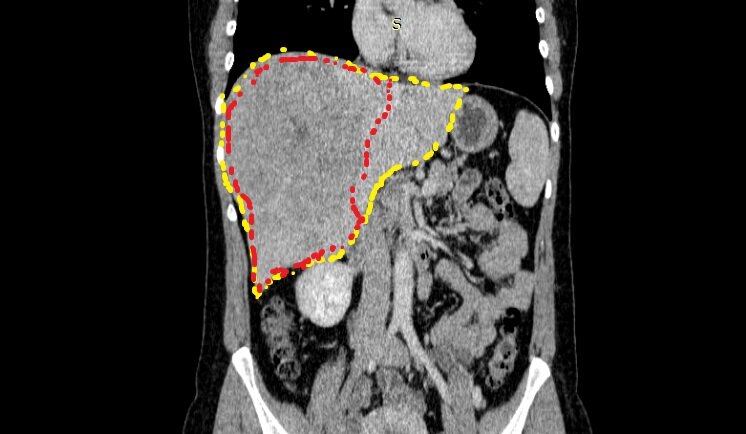

Красным пунктиром обозначены границы опухоли, желтым пунктиром - границы печени. Снимки перед планируемым хирургическим лечением.